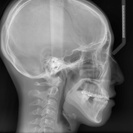

3D CT X-ray

顔面骨や顎関節の形態、歯の形状、

咬合状態などを立体的に把握し診断します。 -

咬合状態などを立体的に把握し診断します。